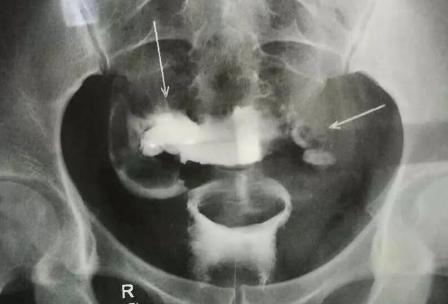

B超可以看出输卵管的状况,B超检查是一种非侵入性的检查手段,可以清晰地显示出输卵管的结构和容积,以及输卵管的通道是否畅通。使用b超可以准确地发现输卵管的闭锁和病变,甚至可以精确地检测出输卵管的形状、厚度、长度、大小、弹性等,检查结果准确可靠,是一种安全、有效的诊断手段。